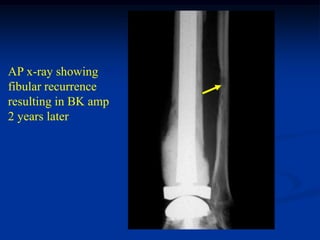

AP x-ray showing

fibular recurrence

resulting in BK amp

2 years later